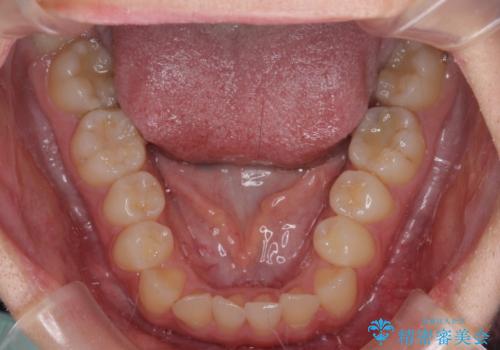

前歯のクロスバイトを短期間で解消 目立たないワイヤー矯正

- 前歯のクロスバイトを治したいとのことで来院された患者様です。

できる限り楽して、短期間で治したいとのことで、ワイヤー装置にて矯正治療を行うこととしました。